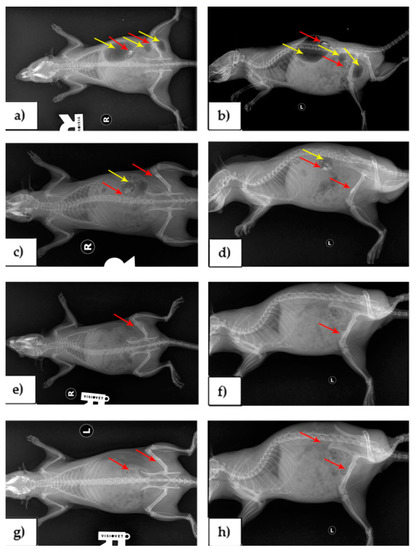

3.2. Imagistic Results